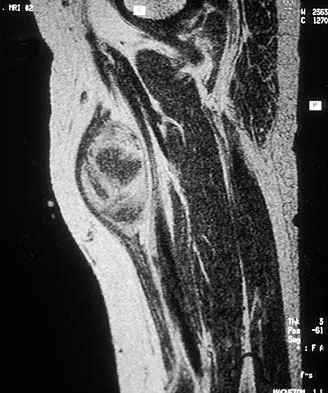

Question 47

A 38-year-old left hand-dominant bodybuilder reports ecchymosis in the left axilla and anterior brachium after sustaining an injury while bench pressing 3 weeks ago. Coronal and axial MRI scans are shown in Figures 16a and 16b. What treatment method yields the best long-term results?

Explanation